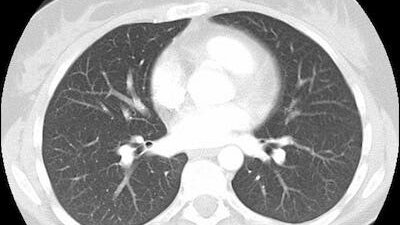

Компьютерная томография лёгких - это неинвазивный метод обследования, который проводят в рамках КТ органов грудной клетки. Цель данного сканирования - максимально визуализировать лёгкие, бронхи, плевру, нижнюю часть трахеи, ткани средостения, нижнюю часть пищевода. В диагностических центрах томография лёгких может проходить по нескольким протоколам: Для взрослых пациентов данное исследование проводится как по назначению врача, так и по личной инициативе. Если диагностику необходимо провести ребёнку, то следует предоставить направление от лечащего доктора...